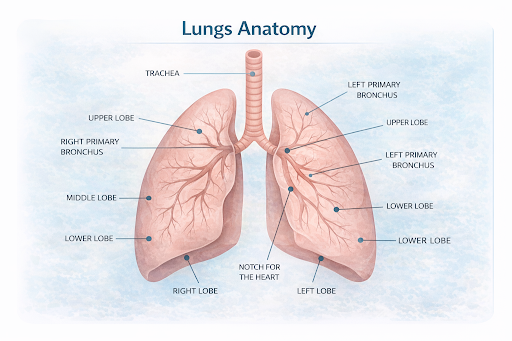

Where It Begins

Lung cancer begins in the lungs, which are located in the chest inside the ribcage. The lungs are made up of soft, spongy tissue and are divided into sections called lobes.

● The right lung has three lobes

● The left lung has two lobes to make space for the heart

Air travels through the bronchi and bronchioles into tiny air sacs called alveoli, where oxygen enters the blood and carbon dioxide is removed.

● The right lung has three lobes

● The left lung has two lobes to make space for the heart

Air travels through the bronchi and bronchioles into tiny air sacs called alveoli, where oxygen enters the blood and carbon dioxide is removed.